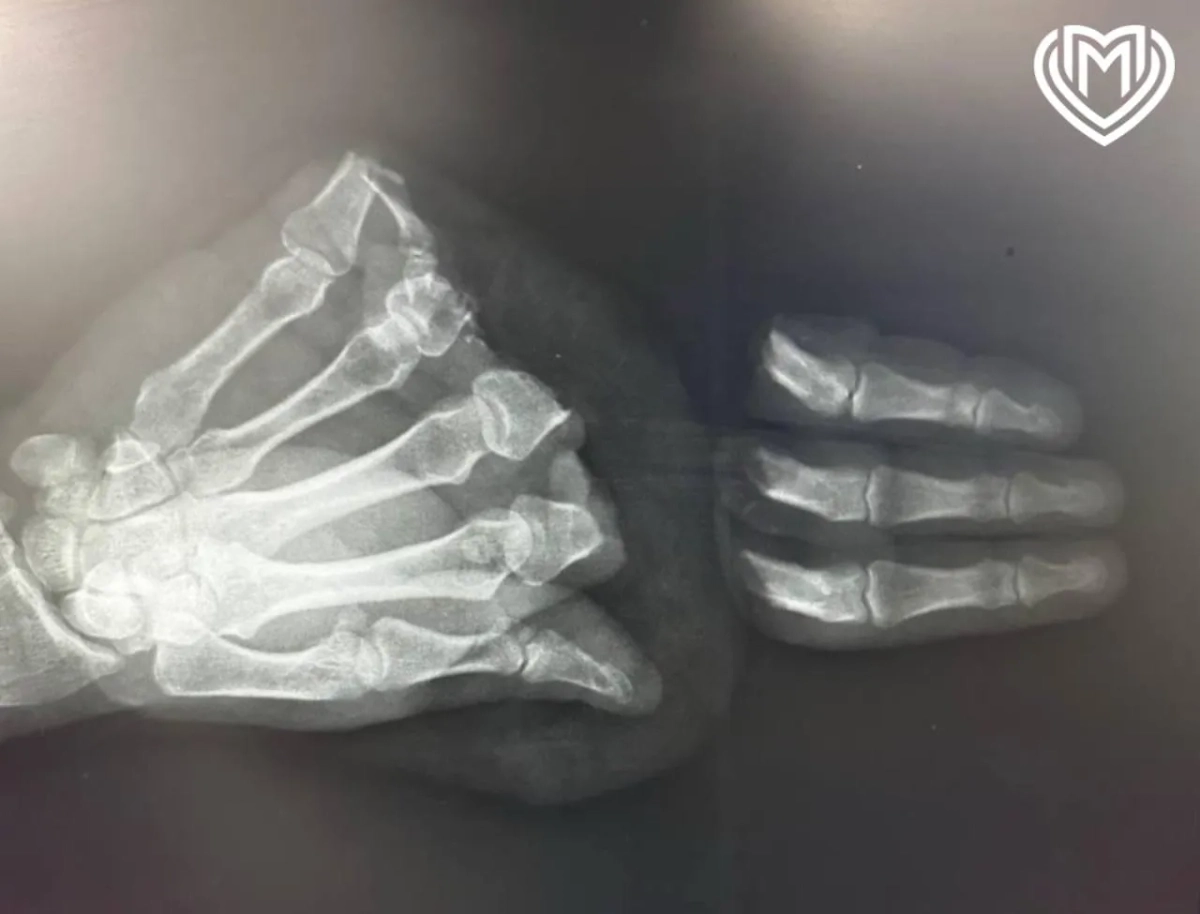

Рентгеновский снимок руки пациента. Фото © Telegram / Московская медицина

Несмотря на все принятые меры, врачам не удалось сохранить мизинец пациента. При этом три других ампутированных пальца были успешно пришиты обратно. Через 10 дней после операции мужчина был выписан из больницы. Теперь ему предстоит период реабилитации и переобучение навыкам письма правой рукой.